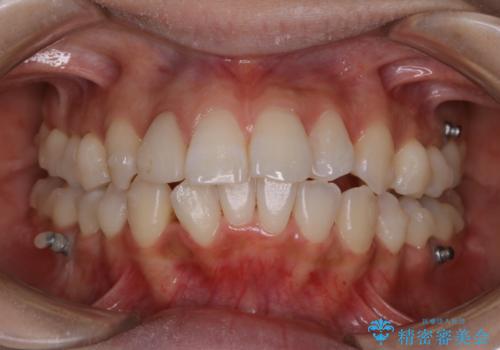

表のワイヤー矯正治療中にPMTCで綺麗に